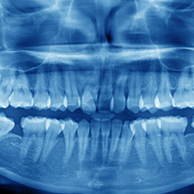

Al-fozan Dental Clinic was established in 1976 as the first private dental clinic in Kuwait, and has grown to be regarded as one of the premier dental clinics in the country. Today, Al-Fozan Dental Center continues to provide the highest standards of dental care, equipped with state of the art technologies and a highly qualified team of dentists.